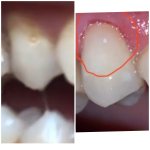

Восстановила мне зуб сбоку.там где десна поднята на фото, но десна опустится.Год назад был у стоматолога, но у него не было оборудования для этого.

до и после .

тут пломба вылетела слева и фото после